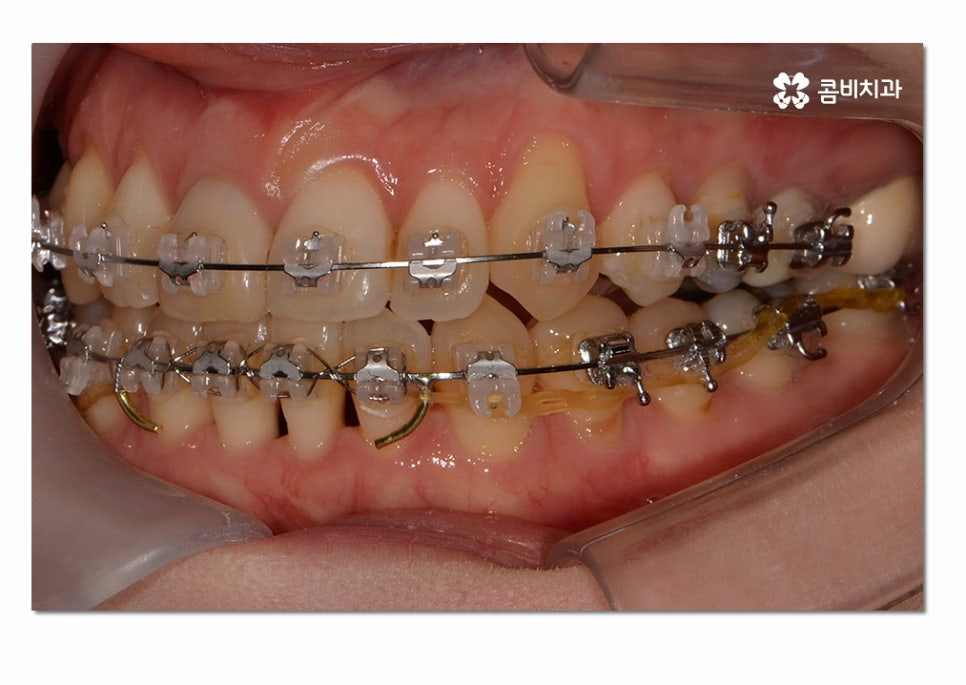

위 사례의 경우에는 3급 부정교합의 케이스로

치열이 맞지 않아 치아의 본래 기능들이 제대로 이루어지지 않고 있는 상태이며

서로 닿지 않아서 식사를 할 때마다 제대로 씹지 못하여

불편함을 느끼는 것은 물론이며 구강관리도 잘되지 않아서

충치가 많이 발생하고 있는 사례였다고 볼 수 있어요.

위 환자분의 경우에는 클리피씨 교정 장치를 통해서 치료가 진행되었으며

발치와 수술 없이 3급 부정교합을 개선한 사례라고 할 수 있어요.

치료에 사용된 클리피씨 장치의 경우 치료 기간을 단축시키고

초기 통증을 감소시킨다는 점과 심미성도 우수한 편이라는 장점이 있는데요.